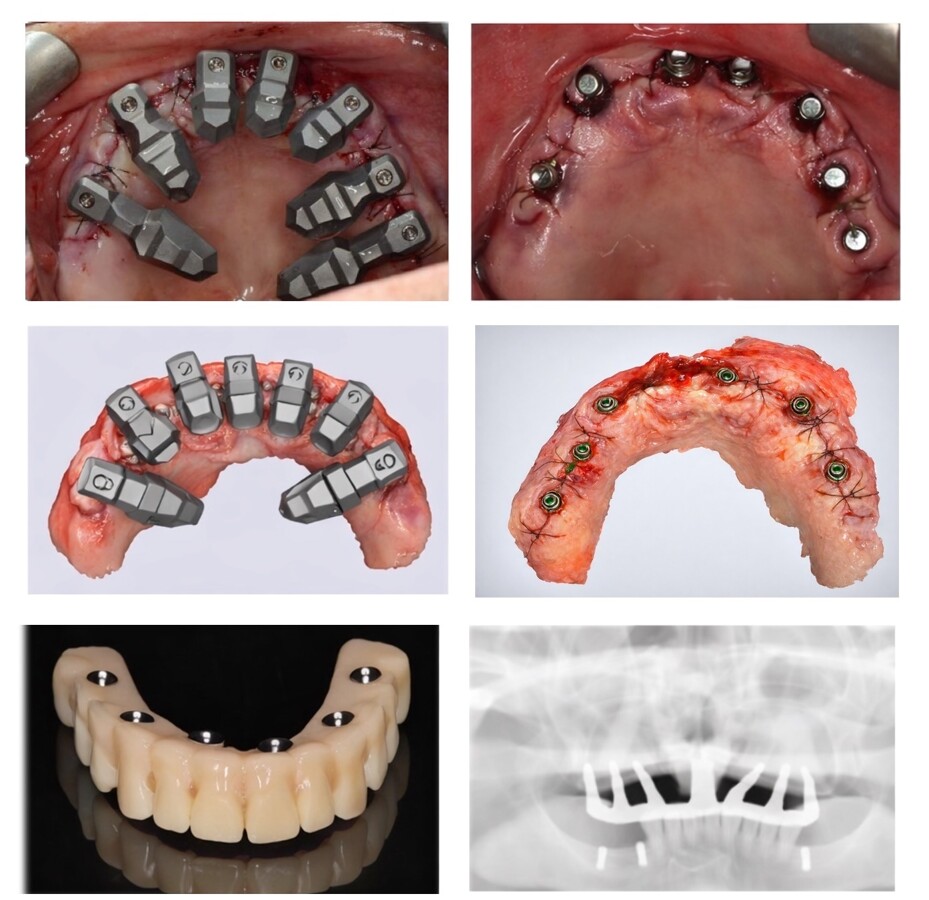

Figura 5. Secuencia del sistema DirectIP en la realidad clínica (arriba) y en la realidad virtual (centro). En las imágenes inferiores, la prótesis y la radiografía de control, donde se observa la pasividad lograda en un caso de arcada completa.